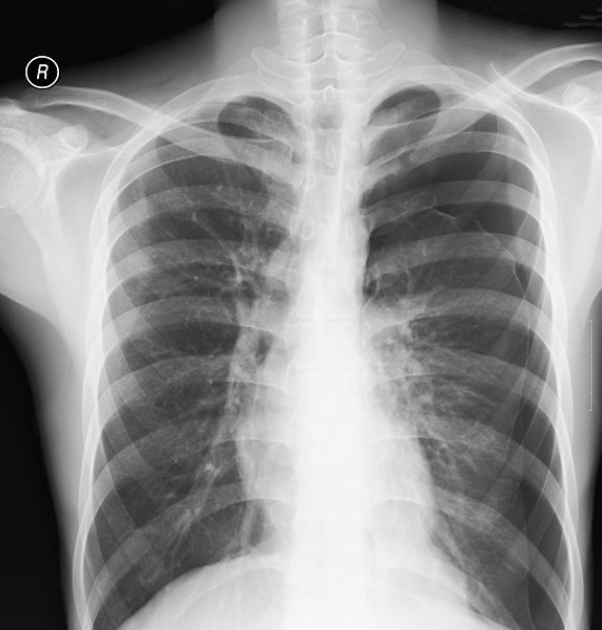

68세 남성이 4일 전부터 점차적으로 심해지는 호흡곤란을 호소하며 병원을 찾았다. 기침이나 가래는 없었다. 환자는 35년 간 하루에 한 갑의 담배를 피워왔으며, 고혈압과 만성폐쇄성폐질환(COPD)으로 치료 중이었다. 혈압은 130/85 mmHg, 맥박은 78회/분, 호흡수는 20회/분, 체온은 36.7℃로 측정되었다. 폐 청진 시 왼쪽 폐에서 호흡음이 눈에 띄게 감소되어 있었다. 가슴 X선 사진을 찍었다. 이 환자의 치료 방법은 무엇인가?

• 청진 상 왼쪽 폐 호흡음이 감소하였고, 가슴 X선 상 왼쪽 폐에 pleural line이 뚜렷이 관찰되어 기흉을 진단할 수 있다.

• COPD 병력은 기흉의 위험인자로, COPD에 합병된 이차성 기흉의 경우 흉관 삽입으로 치료한다.

• 산소 투여: 크기가 작고 증상이 경한 경우 경과관찰 및 산소 투여로 가능하나, 현재 이차성 기흉이며 기흉의 크기도 크므로 흉관 삽관이 필요하다.